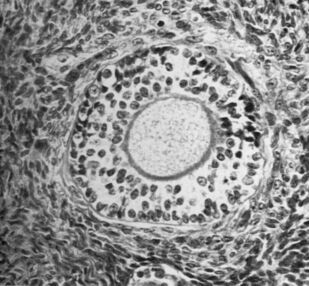

Руководство посвящено прижизненной морфологической диагностике опухолей яичников. В нем приводятся клинико-морфологические характеристики доброкачественных, пограничных и злокачественных новообразований, а также неопухолевых процессов, которые нередко могут имитировать опухоли яичников. Наибольшее внимание уделено дифференциальной диагностике этих заболеваний. Отдельная глава посвящена эмбриогенезу и возрастным особенностям яичников, знание которых существенно расширяет дифференциально-диагностические возможности. Изложение основного материала сопровождается описанием конкретных правил обработки биопсийного и операционного онкологического материала.